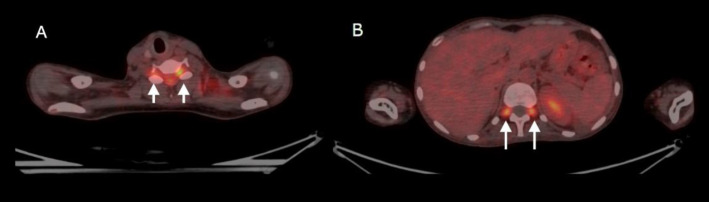

Pineal gland tumors are significant despite being rare (<1%) among all brain tumors. Germ cell tumors are the most common among the pineal gland tumors. Often affecting young adults, pineal gland germ cell tumors are hard to diagnose due to different symptoms and potential spread. But they rarely show leptomeningeal spread and extracranial metastases. Other differentials include primary tumors of the pineal region, Pineal gliomas, and metastases. The leptomeningeal spread of these tumors has not been studied so far. Conventional radiological imaging modalities are routinely used to diagnose and evaluate these tumors. We report a case here showing a pineal gland tumor with leptomeningeal spread detected by 18F-FDG PET/CT. Our case shows how pineal gland tumors can behave unusually and how 18F-FDG PET/CT can be crucial for accurately assessing the extent of the disease in the body to provide effective treatment. This case report illustrates the rare type of spread of pineal gland tumor and how 18F-FDG PET/CT helps detect this rare type of metastasis, thereby helping in prognostication and deciding further treatment of the patient.